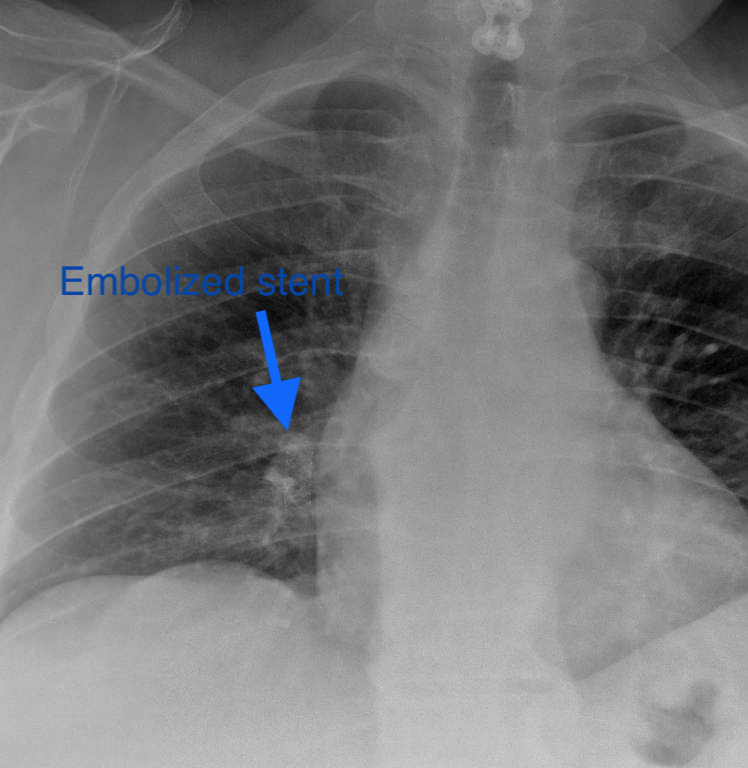

Pt presented to ED with CP, SOB. CXR shows embolized venous stent from OSH. Retrieved with 3 snares, 4 forceps, OR on standby,

@UABVascular help, 26F sheath, extra IR. Immediate symptom relief@SIRspecialists@SIRRFS@JVIRmedia#withoutascalpel#MIIPS#venous#embolize@uab_irpic.twitter.com/WpoUEt3P7z